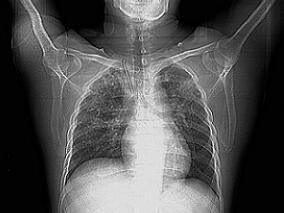

1小时条评论71岁男性,反复胸痛半月余。患者急性心肌梗死发病5个月后复查心脏彩超示心尖部室壁瘤消失,心功能明显改善,左心房、左心室恢复至正常范围。胸片可见心脏明显缩小,心胸比恢复至正常范围。需与其他可能导致心尖部膨出的疾病相鉴别,如心尖球形综合征。您知道如何排除...